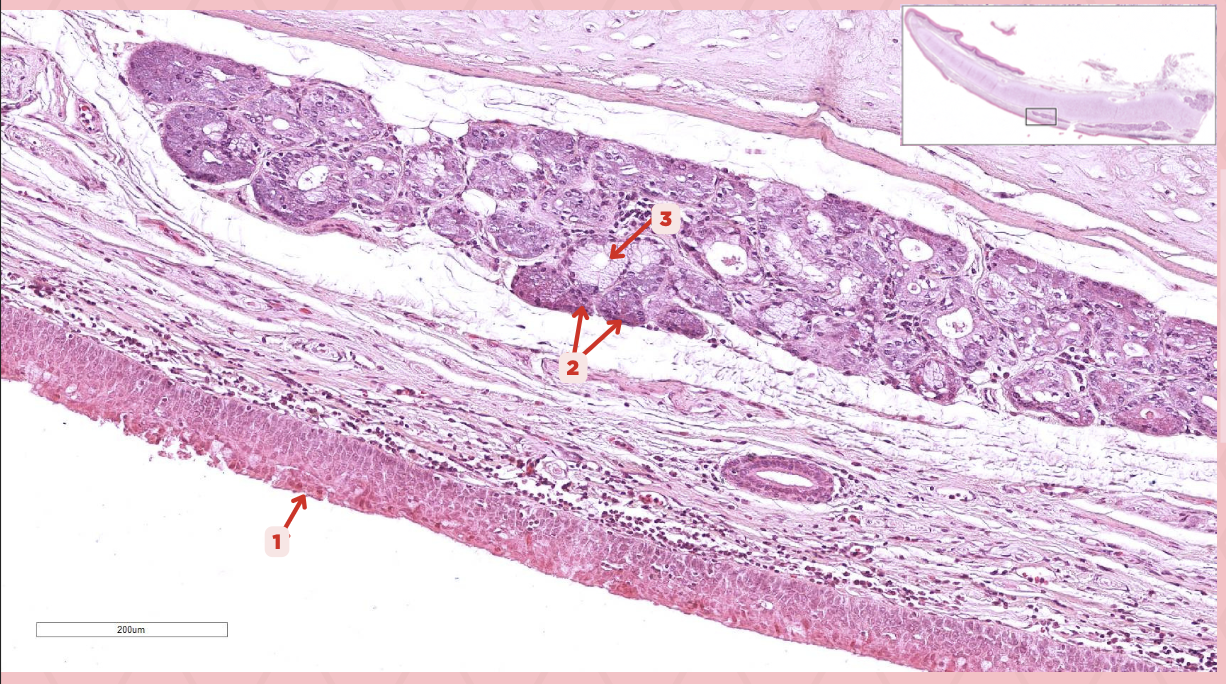

Epiglottic Elastic Cartilage

Identify the structure labeled as 1.

Serous Gland

What is the gland at #2?

Mucous Glands

What is the gland at #3?

Respiratory Epithelium

Identify the structure labeled as 1.

Laryngeal Ventricle

Space that separates the true and false vocal cords (#4)